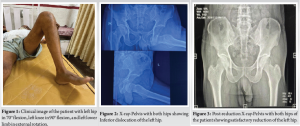

A 60-year-old male patient was brought to the emergency room following an alleged history of a fall from 10 feet height following which the patient sustained injury to the left hip. Patient was conscious, oriented, and vitally stable (Glasgow Coma Scale- 15/15, blood pressure- 130/90 mm of Hg, Pulse- 88 bpm, respiratory rate- 20/min, SpO2– 99% on room air). The patient was thoroughly examined in the emergency room for any other systemic injuries. The patient was lying supine with left hip in 70° flexion, left knee in 90° flexion, and left lower limb in external rotation (Fig.1).

Patient was given intravenous analgesics and fluid support and shifted to the X-ray room, where X-ray revealed an inferior hip dislocation left side (Fig. 2).

The patient was taken to the emergency operation theatre and closed reduction under short-duration general anesthesia was done by giving sustained traction toward the head, followed by gradually extending the thigh with internal rotation at the hip joint. Following reduction Left lower limb was immobilized using a long knee immobilizing brace. Patient was taken to the X-ray room and reduction was confirmed (Fig. 3).